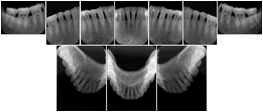

Intra-oral radiography typically involves acquisition of multiple images of various parts of the dentition. Many digital radiographic systems offer customized templates that are used for displaying the images in a study on the screen. These templates may also be referred to as mounts or view sets. The Structured Display Object represents a standard method of encoding and exchanging the layout and intended display of Structured Displays. A structured display object created in this manner could be stored with a study and exchanged with images to allow for complete reproduction of the original exam.

1. A patient visits a General Dentist where a Full Mouth Series Exam with 18 images is acquired. The dentist observes severe bone loss and refers the patient to a Periodontist. The 18 images from the Full Mouth Series along with a Structured Display are copied to a DICOM Interchange CD and sent with the patient to see the specialist. The Periodontist uses the CD to open the exam in his Dental Radiographic Software and consults via phone with the General Dentist. Both are able to observe the same exam showing the images on each user's display using the exact same layout.

Intra-oral Full Mouth Series Structured Display

Figure OO-1. Intra-oral Full Mouth Series Structured Display